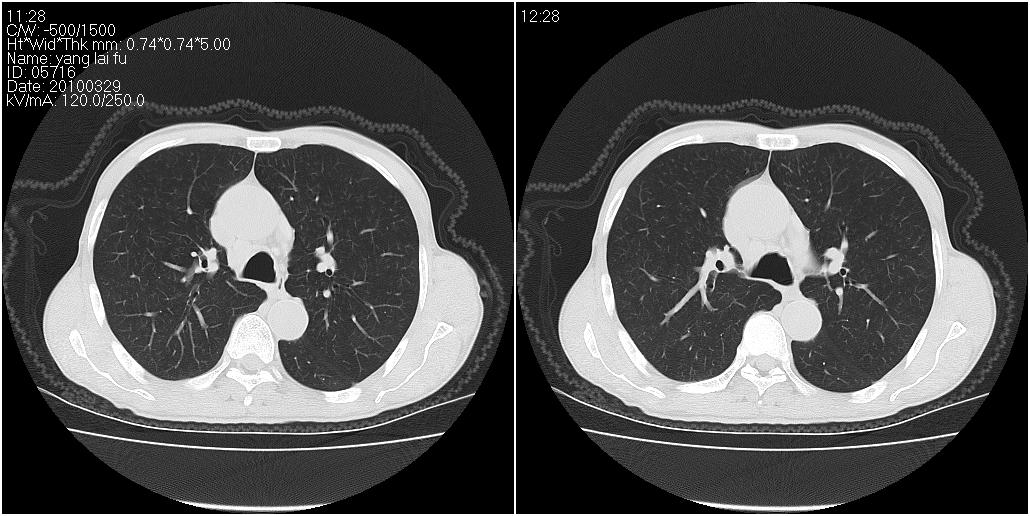

标题: CT25416:男性,70岁。胸片发现右下肺斑片状阴影 [打印本页]

标题: CT25416:男性,70岁。胸片发现右下肺斑片状阴影

以下是ct检查的情况:

考虑右肺下叶炎症可能性大?未除占位,建议增强。右下肺肺不张

炎症?占位建议纤支镜或增强检查

右下肺阻塞性肺炎!建议纤支镜!